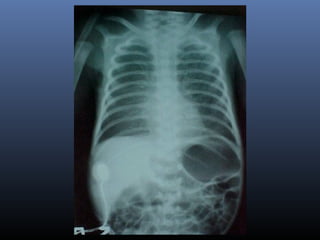

 Achados radiológicos:

Quadros leves:

Infiltrados em formas de estrias.

Pequenos nódulos

Hiperinsuflação pulmonar

Quadros moderados e graves:

Infiltrações nodulares grosseiras e

difusas.

Áreas de hiperinsuflação alternadas

com áreas de atelectasia.

Síndrome de Aspiraçãode Mecônio  Achados radiológicos: Quadros leves: Infiltrados em formas de estrias. Pequenos nódulos Hiperinsuflação pulmonar Quadros moderados e graves: Infiltrações nodulares grosseiras e difusas. Áreas de hiperinsuflação alternadas com áreas de atelectasia.